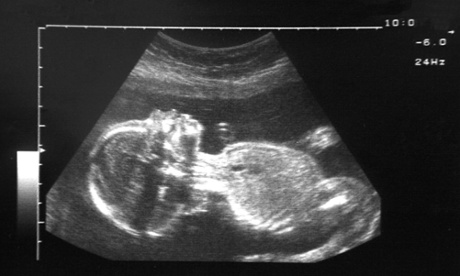

An ultrasound of a healthy 20-week foetus

An ultrasound scan of a healthy 20-week foetus. The children of heavy drinkers were more likely to be hyperactive and have behavioural and emotional problems. Photograph: Craig Holmes/Alamy

The children of heavy drinkers were more likely to be hyperactive and have behavioural and emotional problems, but the babies who were born to light drinkers suffered no ill effects.